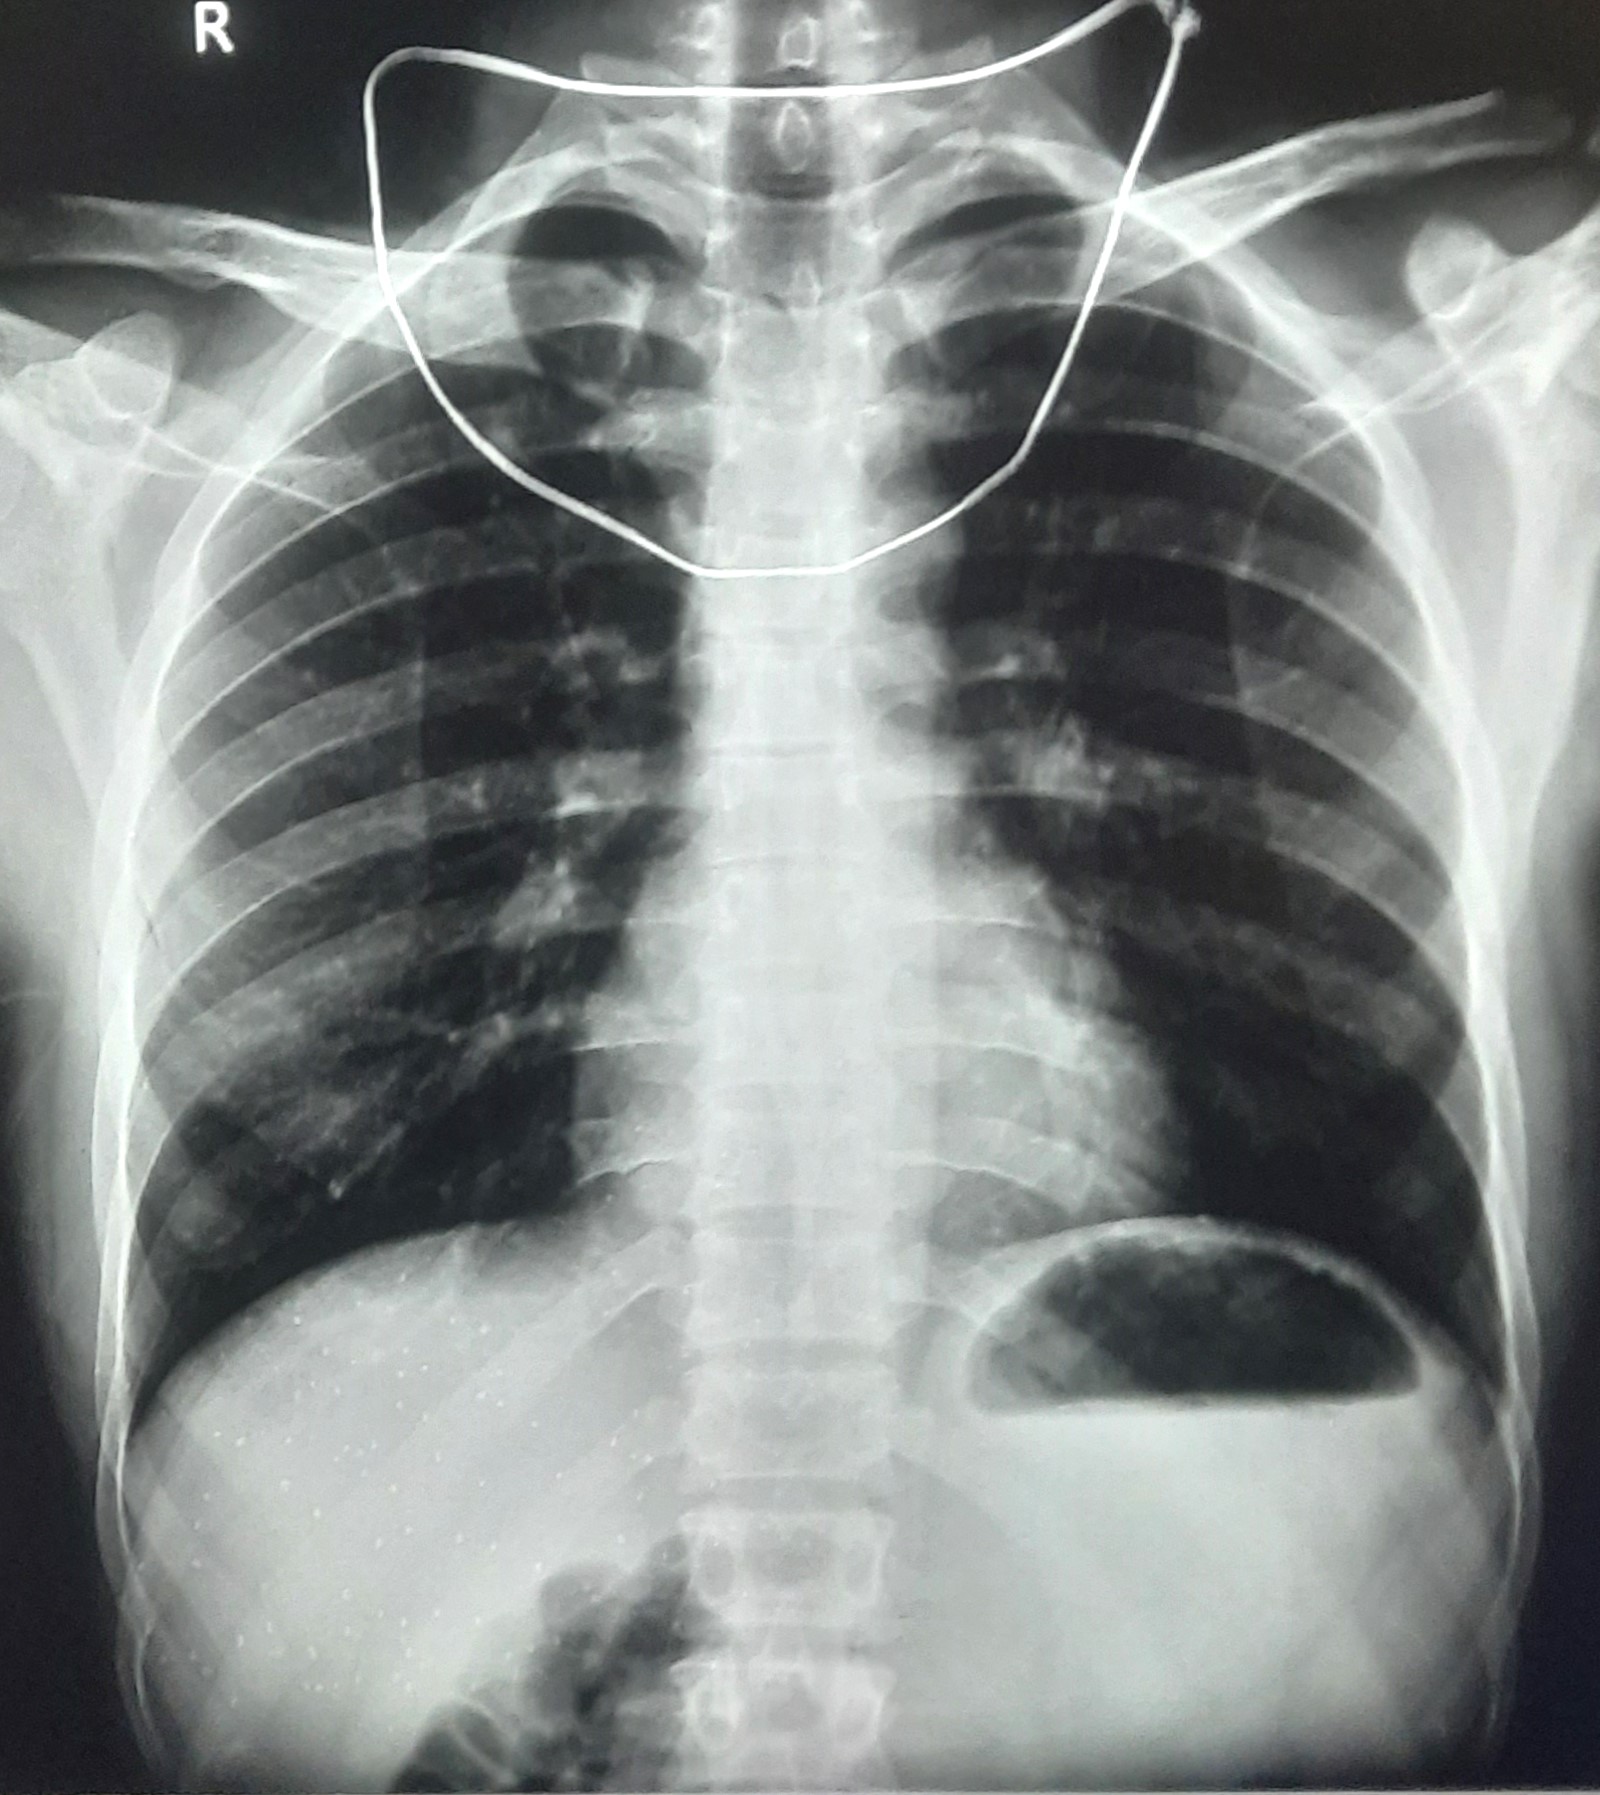

| 262 | IGGMC, Nagpur, Nagpur | P2 | 29-4210 | Mohamad Aslam | Consent taken on Paper | 35 Yrs. |

Provisional Diag : C/O Extra Pulmonary TB

Final Diag : FIBROSIS |

TB Case (Confirmed) | S/O RETICULAR OPACITIES NOTED IN RIGHT UPPER & MIDDLE ZONE/ QUERY FIBROSIS | Abnormality visible on x-ray |